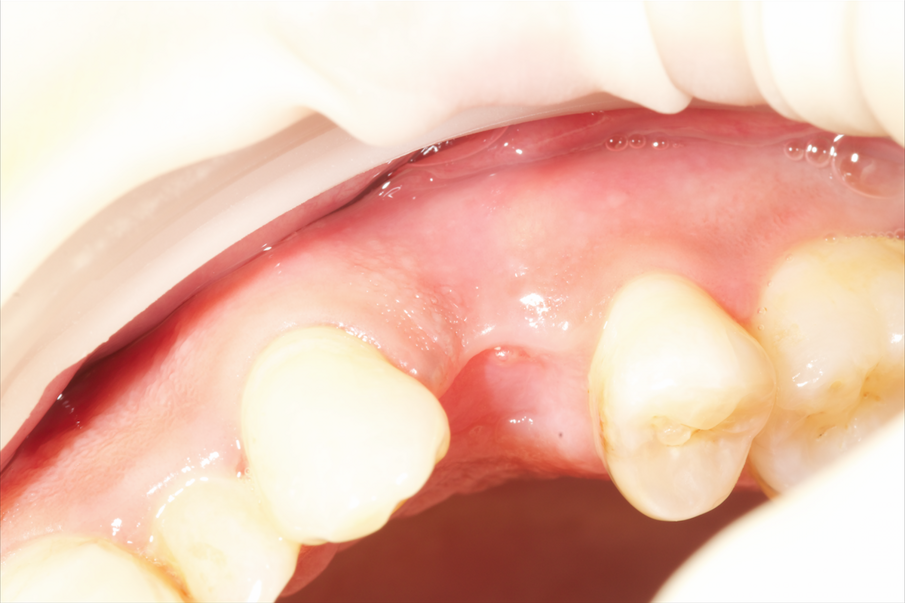

Fig. 9 - Situazione dopo sei giorni.

Fig. 10 - Rimozione della sutura dopo sei giorni.

Fig. 11 - Situazione due settimane dopo: buona guarigione senza interferenze da parte del biomateriale.